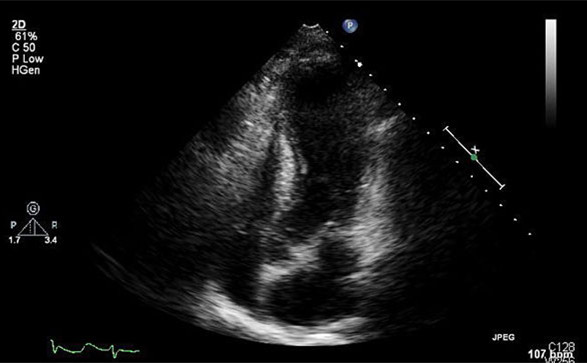

[超声心动图]

经胸超声心动图是诊断TCM室壁运动异常的快速方式,特别是诊断LV运动减低或心室中部和心尖部的运动缺失。这些室壁运动异常超出了任何单一冠状动脉的分布区域。左室射血分数(LVEF)可以通过超声心动图、CMRI或左心室造影来估算。

超声心动图显示,TCM患者心尖部在收缩期无运动,射血分数为40%。